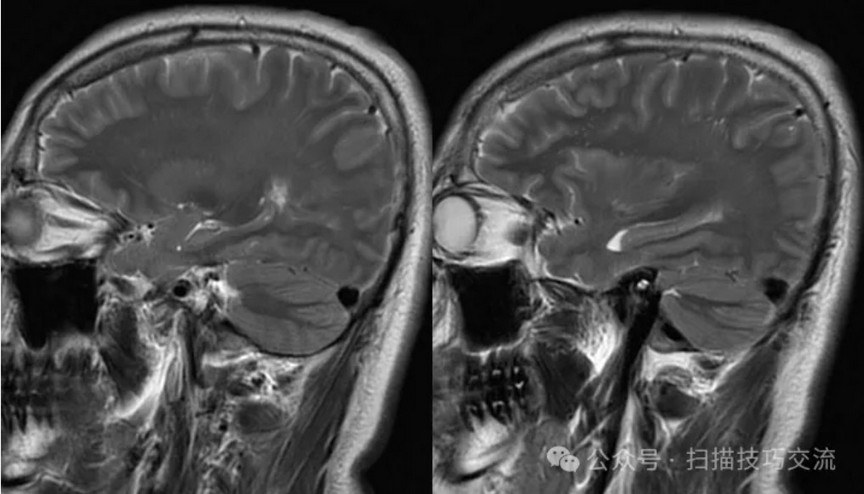

•男性,29岁,已婚 •头痛伴头晕恶心呕吐20余天 •现病史:患者于20天前,熬夜饮酒后出现头痛,为胀痛,头痛剧烈,伴头晕恶心呕吐。就诊于当地医院,未作出明确诊断。现症状有所缓解,于平卧位时无明显不适,坐位或直立式上述症状加重。急诊以“头痛”收入卒中中心。病程中无视物模糊,无饮水呛咳,无吞咽困难,无抽搐发作等症状。自发病以来睡眠欠佳,近3日未进食,二便正常。近期体重未见明显变化。 •既往史:平素健康,过敏史或不良反应药物反应史无。外伤史无。手术史无。传染病史无。预防接种史无。其它无。

•汗腺分泌:正常,皮肤划痕正常反应。 •尿便障碍:无。性功能障碍无。 •专科情况:正常。不逐一罗列。 •辅助检查:01-05颅脑CT提示:1,上矢状窦、双侧横窦密度较高,请结合临床,必要时进一步检查;2,双侧脑室后角可疑稍高密度影,右顶叶局部脑沟密度可疑增高,建议进一步检查。 •初步诊断:静脉窦血栓

临床申请:颅脑平扫,静脉成像,磁敏感成像,颅内静脉血管黑血成像。